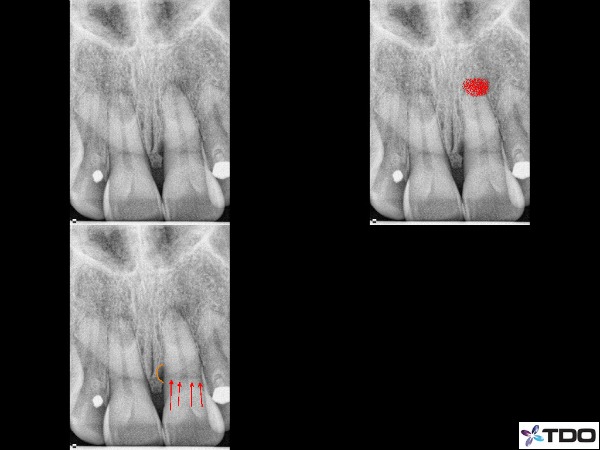

–lateral / furcal lesion caused by a primarily endodontic infection that creates the lateral and periodontal defect (figure 2,3)

Fig.2 Here is a case I treated about 1.5 years ago. The illustration shows the significant lateral and distal bone loss on the distal root of #18. The 8 month recall is on the bottom left side with red arrows showing excellent bone healing. This tooth went from a 2 mobility to rock solid before I had completed the case with 2 months of CaOH in the canals.

Fig. 3 This was a retreatment case by Dr. Sherman in which he medicated the canals over 3 appointments using CaOH. The upper left is the pre-operative x-ray. Upper right is the immediate post-operative x-ray and the lower x-ray is the 1 year recall. There has been significant bone fill into the furcation which will continue to improve over time.